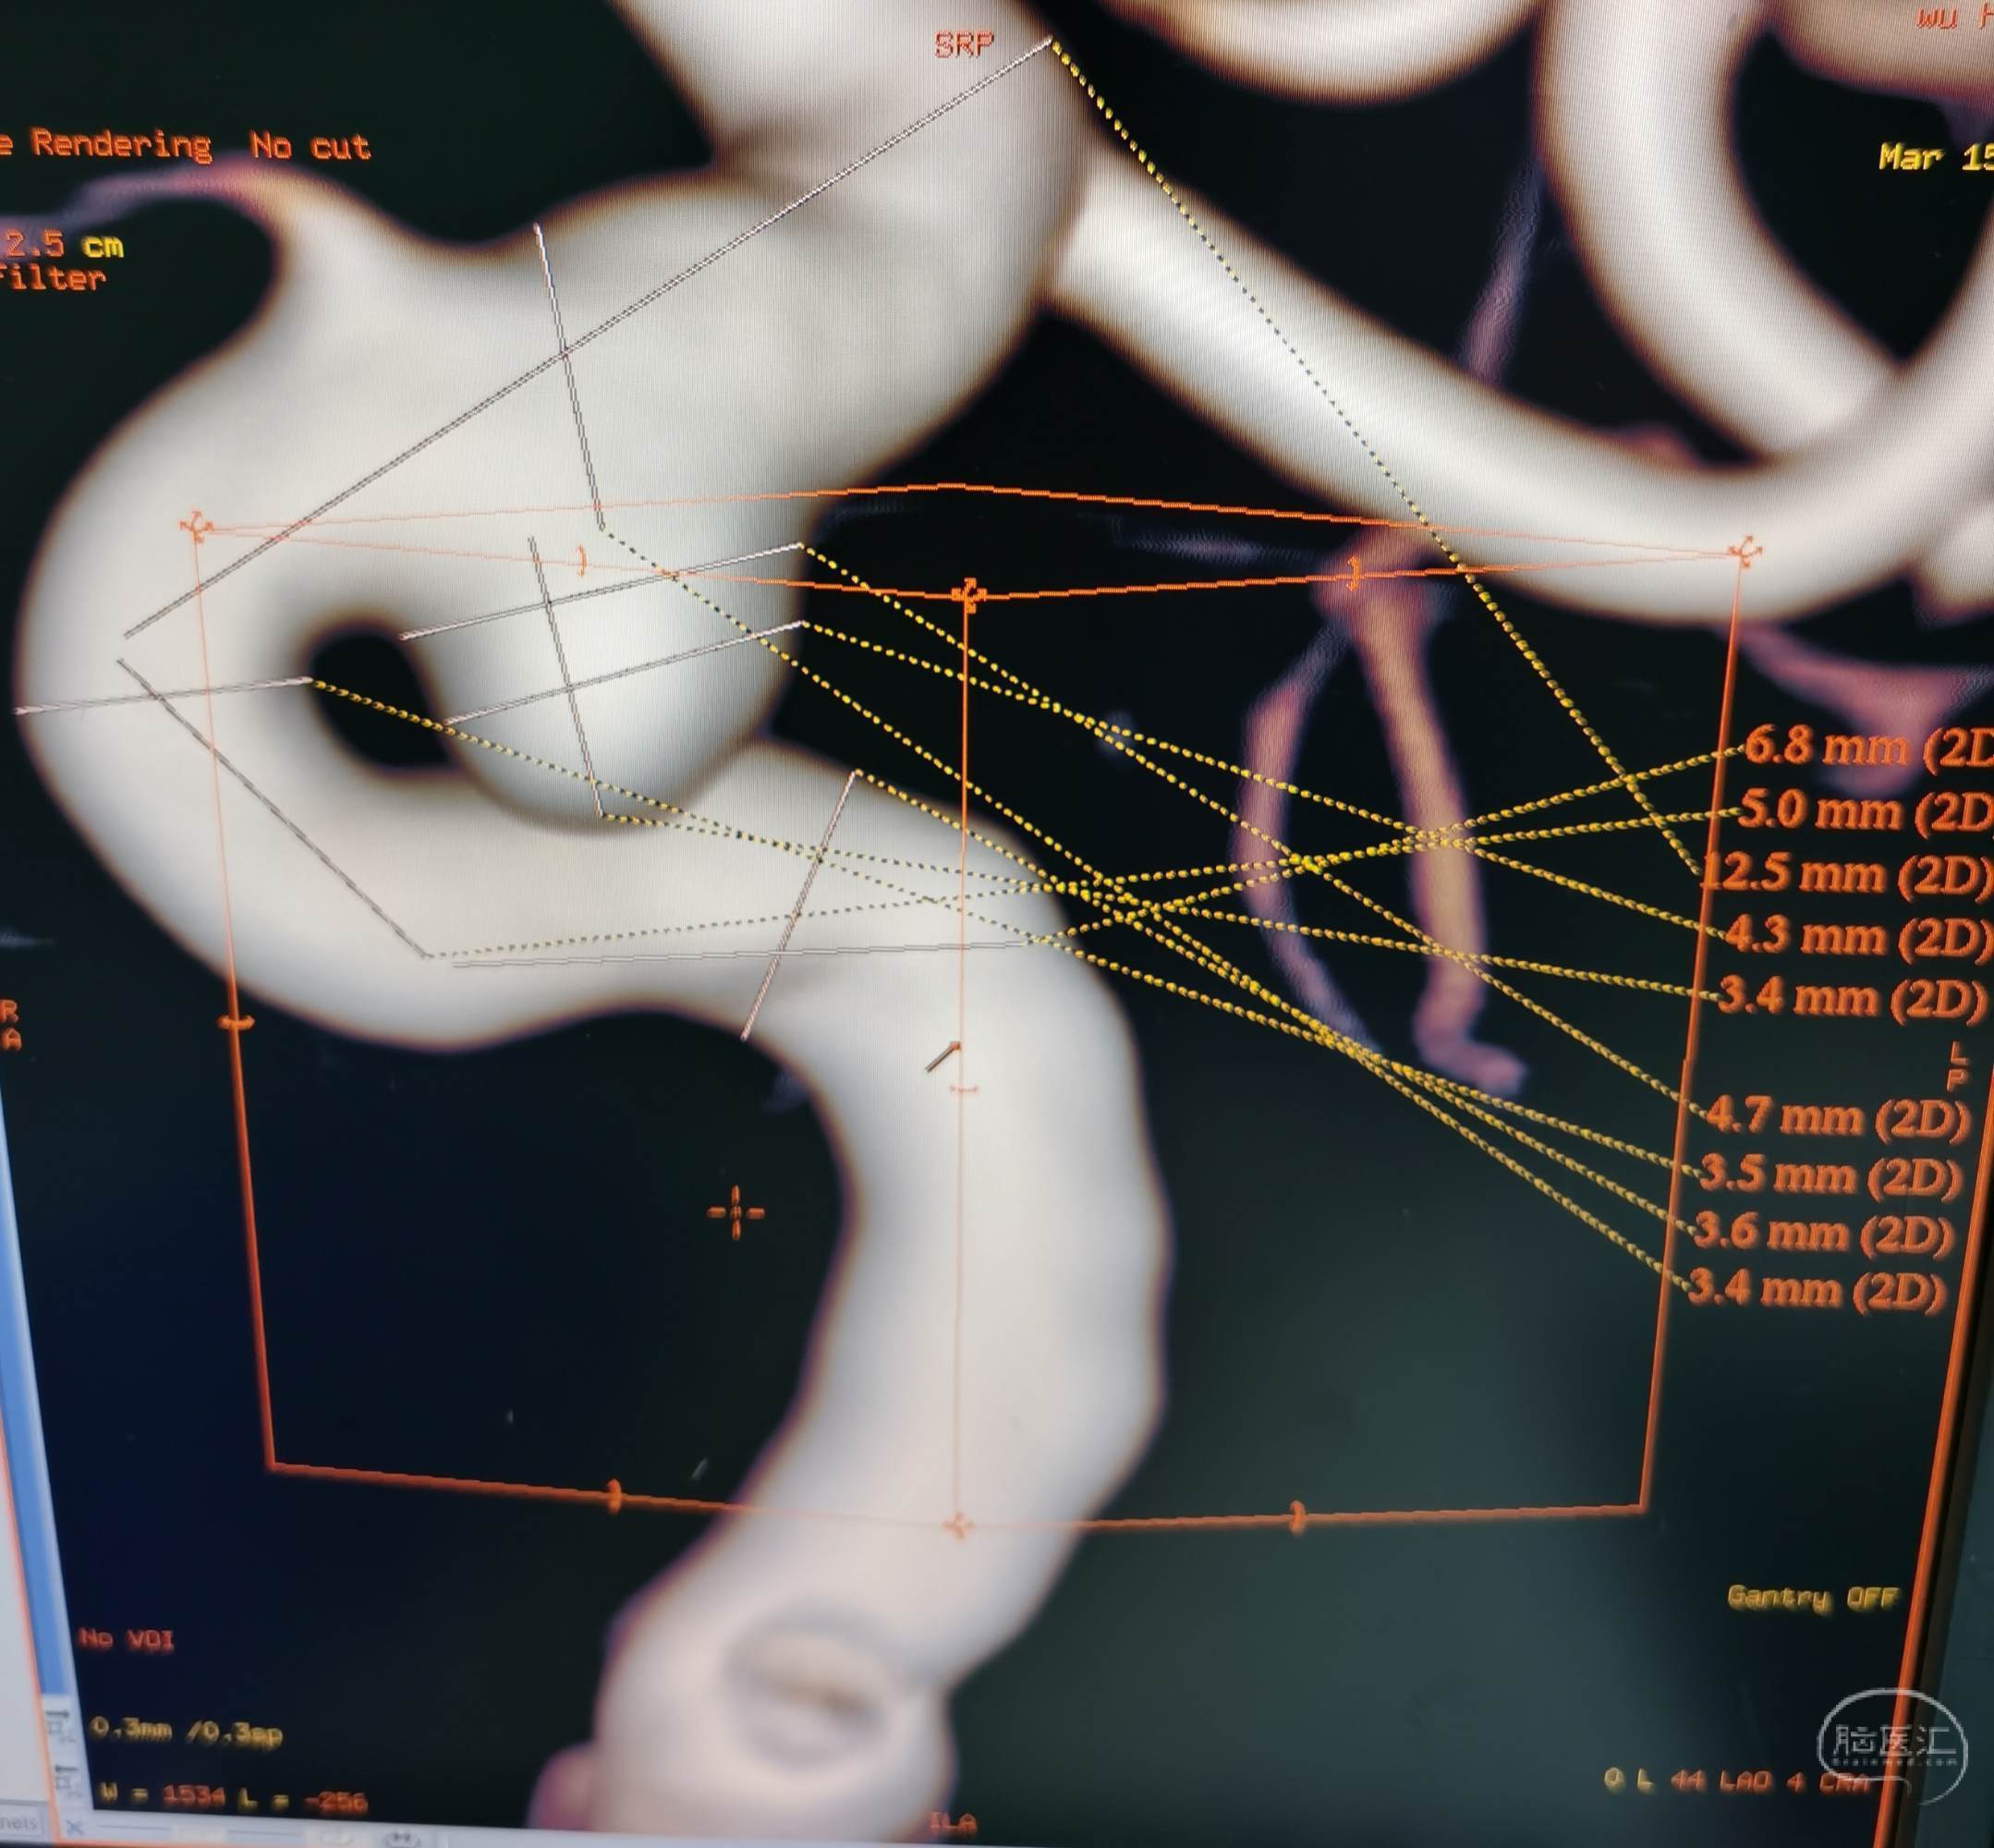

病例2 中年女性,诊断:颅内动脉瘤(C6段)。

DSA示右侧眼段动脉瘤。

3D示动脉瘤大小4.3×4.7×3.6mm。